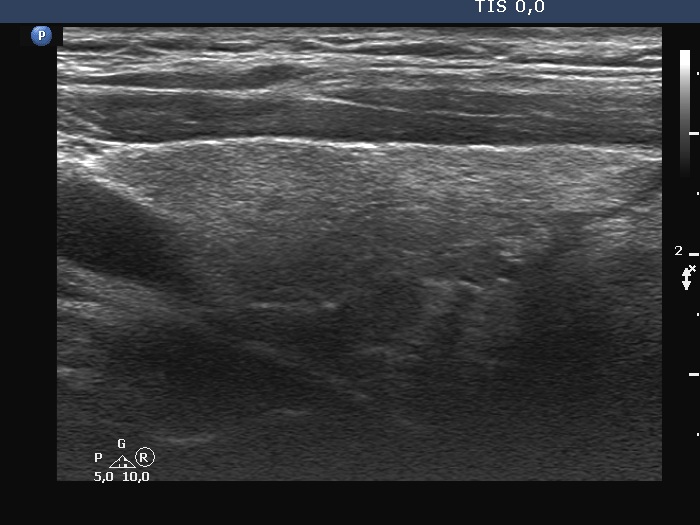

Examination 7 months later (second row of images):

Clinical presentation: The patient became asymptomatic within 12 hours after the first dose of methyl-prednisone and remained so.

Palpation: no abnormality.

Laboratory tests: TSH 1.03 mIU/L, FT4 14.2 pM/L, CRP 0.7 mg/L.

Ultrasonography: Both the size of the nodule and the extent of hypoechoic areas have decreased. An isoechoic nodule has appeared which was obscured by hypoechogenicity in the previous study. The vascularity was still very scanty.

Suggestion. Follow-up in 2 years.